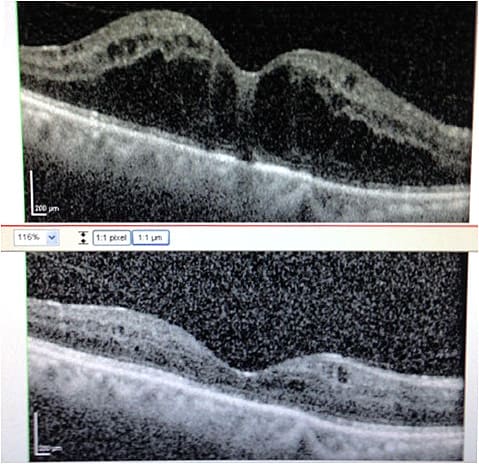

OCT scan is repeated four weeks after initiation of topical therapy (Figure 2). If CME is persistent, I give 1 ml of sub-Tenon’s kenalog and continue topical NSAIDs while stopping topical difluprednate.